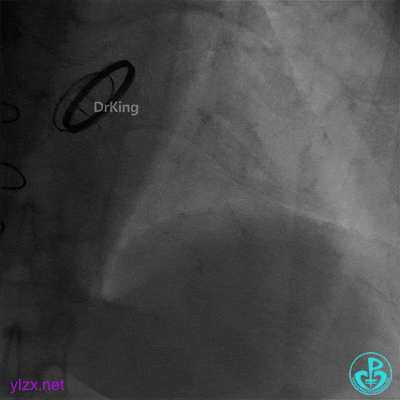

05 急诊冠脉造影

前降支血流3级,前降支近段、对角支开口大量血栓,回旋支开口闭塞。